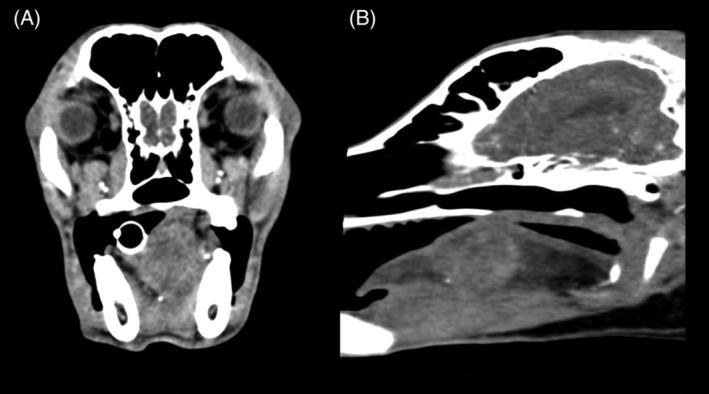

Retrospective study. Dogs with a final diagnosis of visceral or muscular HSA that underwent whole body CT scan were enrolled in the study. Final diagnosis of primary tumor and SMMs was reached by histology, cytology, or both. Signalment, clinical signs, localization of the primary lesion, and metastases characteristics were reviewed.

Sixty-one dogs met the inclusion criteria. Skeletal muscle metastases were detected in 15 dogs (24.6%) and all of these dogs had also metastases in ≥1 sites. Presence of SMMs was significantly higher in males but was not significantly related to age, neuter status, breed, localization, and dimensions of the primary tumor. Nine of 15 (60.0%) dogs with SMMs showed lameness or reluctance to move whereas these signs were not recorded in any of the 42 dogs without SMMs (P < .001).

Prevalence of SMMs in our population of dogs with HSA was higher in comparison to previous studies in the human and veterinary medical literature. Whole body CT is recommended for staging of dogs with HSA, because SMMs could be missed by clinical examination and traditional diagnostic imaging modalities.